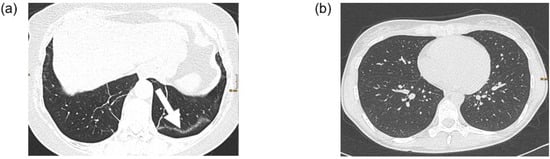

Figure 2 shows an example of a patient with possible post-COVID-19 features (subpleural bands) and a patient with a normal chest CT scan.

Figure 2. Two examples of chest CT scans. (a) CT examination in supine position of a 62 year old female patient with post-COVID-19 syndrome. The lung parenchyma shows subpleural bands (arrow) in the left lower lobe as sign of residual post-COVID changes. (b) CT examination in prone position of a 32 year old female patient with post-COVID-19 syndrome. The lung parenchyma is unremarkable.